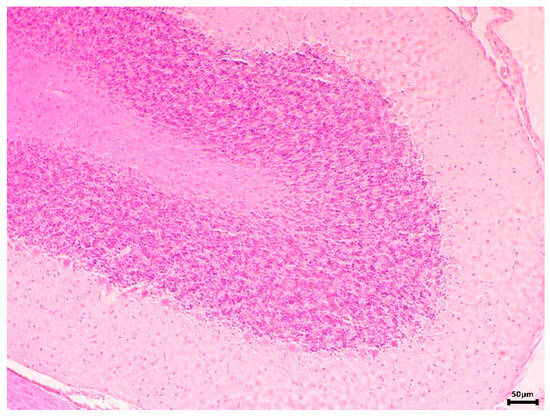

2.6.3. Histopathological Examination

3.2.2. In Vivo Experiments with Old Wistar Rats